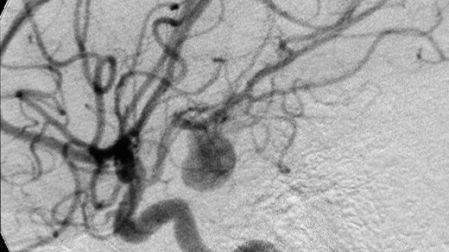

¿Qué es una aneurisma?

Un aneurisma cerebral es una protuberancia en un vaso sanguíneo en el cerebro, causada por una debilidad en la pared del vaso sanguíneo, generalmente donde se ramifica. A medida que la sangre pasa a través del vaso sanguíneo debilitado, la presión arterial hace que una pequeña área se abulte hacia afuera como un globo.